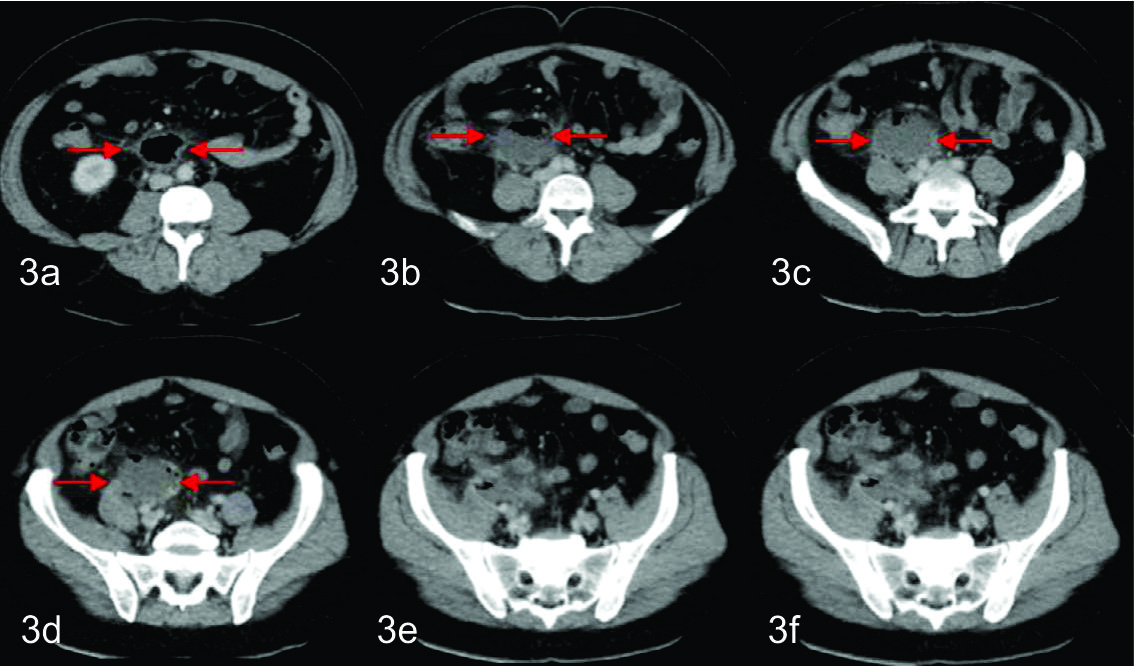

La misma, por su sector superior derecho se extendía hasta la fosa iliaca reconociéndose a dicho nivel tres pequeñas imágenes calcicas redondeadas, que fueron interpretadas como apendicolitos, elemento semiológico fundamental, para arribar al diagnóstico de apendicitis aguda complicada con absceso pelviano. Con dicho planteo diagnostico se discute junto con los cirujanos de guardia tratantes la posibilidad de realizar manejo percutáneo del absceso como tratamiento inicial, y determinan en la evolución la eventualidad de realizar cirugía definitiva. El procedimiento fue realizado bajo guía tomográfica con el paciente en decúbito supino, Se valoro ventana de acceso y se procedió a topografiar el sitio de abordaje en piel, que fue a nivel de hipogastrio. Se procedió a colocar el drenaje bajo técnica de Trocar, utilizándose un drenaje multipropósito 14 F. El mismo se dejó abierto a bolsa colectora con llave de tres vías. El material obtenido fue francamente purulento y se tomaron muestras del mismo para análisis bacteriológico, cultivando flora polimicrobiana.

En el control tomográfico posterior, realizado a los 7 días del procedimiento, se reconoce el catéter de drenaje ingresando por la pared anterior del abdomen, el cual se dirige caudomedial con su extremo en el fondo de saco de Douglas, sin evidencia de colección residual. Se decide realizar prueba terapéutica cerrando el drenaje. Dada la buena evolución, el mismo es retirado a las 48 hs.

En los cortes más caudales se reconoce al ciego en su topografía habitual y de él se observa emerger de su pared posterior, al apéndice cecal, el cual es de aspecto patológico, tomando contacto con la colección antes descripta. Con el planteo de apendicitis aguda complicada con colección infectada se discute junto con cirujano tratante la eventual posibilidad de poder realizar tratamiento percutáneo, el cual se determinó que era pasible de ser efectuado en este paciente. Se realizó nuevamente bajo guía tomográfica con el paciente en decúbito supino. Se procedió a topografiar el sitio de abordaje en piel a nivel de flanco derecho y se coloco drenaje multipropósito 12 F bajo técnica de Seldinger, el cual se dejo abierto a bolsa colectora con llave de tres vías. El material obtenido fue purulento, algo hemorrágico, con grumos, del cual se tomaron muestras para análisis bacteriológico, cultivando gérmenes gram negativos. En el control tomográfico posterior, a los cinco días de colocado el drenaje, se necesitó un reposicionamiento del mismo, pudiendo evacuar totalmente la colección residual en la evolución. Luego de 15 días de colocado el drenaje, con levados diarios en los últimos 7 días, una vez resuelta la colección, sin elementos clínicos ni paraclínicos humorales de infección, se decide retirar el drenaje, presentando el paciente una excelente evolución.

En estos dos casos que se presentaron, ambos drenajes fueron colocados bajo guía tomografía debido a la falta de ventana acústica en parte por la profundidad donde se topografiaban las colecciones a drenar.

En la segunda modalidad (Trocar) , se procede a introducir el drenaje armado y mojado sobre una aguja metálica, accediendo de esta forma directamente a la colección. El método de abordaje elegido dependerá básicamente de la ubicación de la colección y la preferencia del operador. En ambos casos se realizo una tomografía computarizada de control confirmando de esta manera el correcto posicionamiento del catéter.